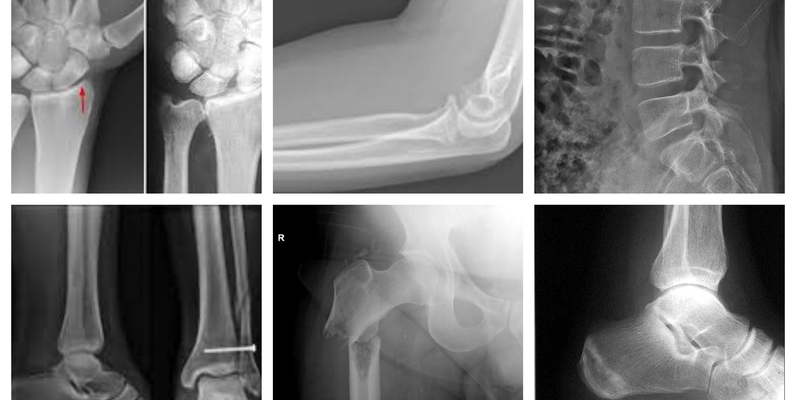

多区域骨折 X 射线数据集

该数据集包含骨折和非骨折的 X 射线图像,涵盖所有解剖身体区域,包括下肢、上肢、腰椎、臀部、膝盖等。数据集分为训练、测试和验证文件夹,每个文件夹包含骨折和非骨折的射线图像,共 10,580 张放射图像(X 射线)数据。